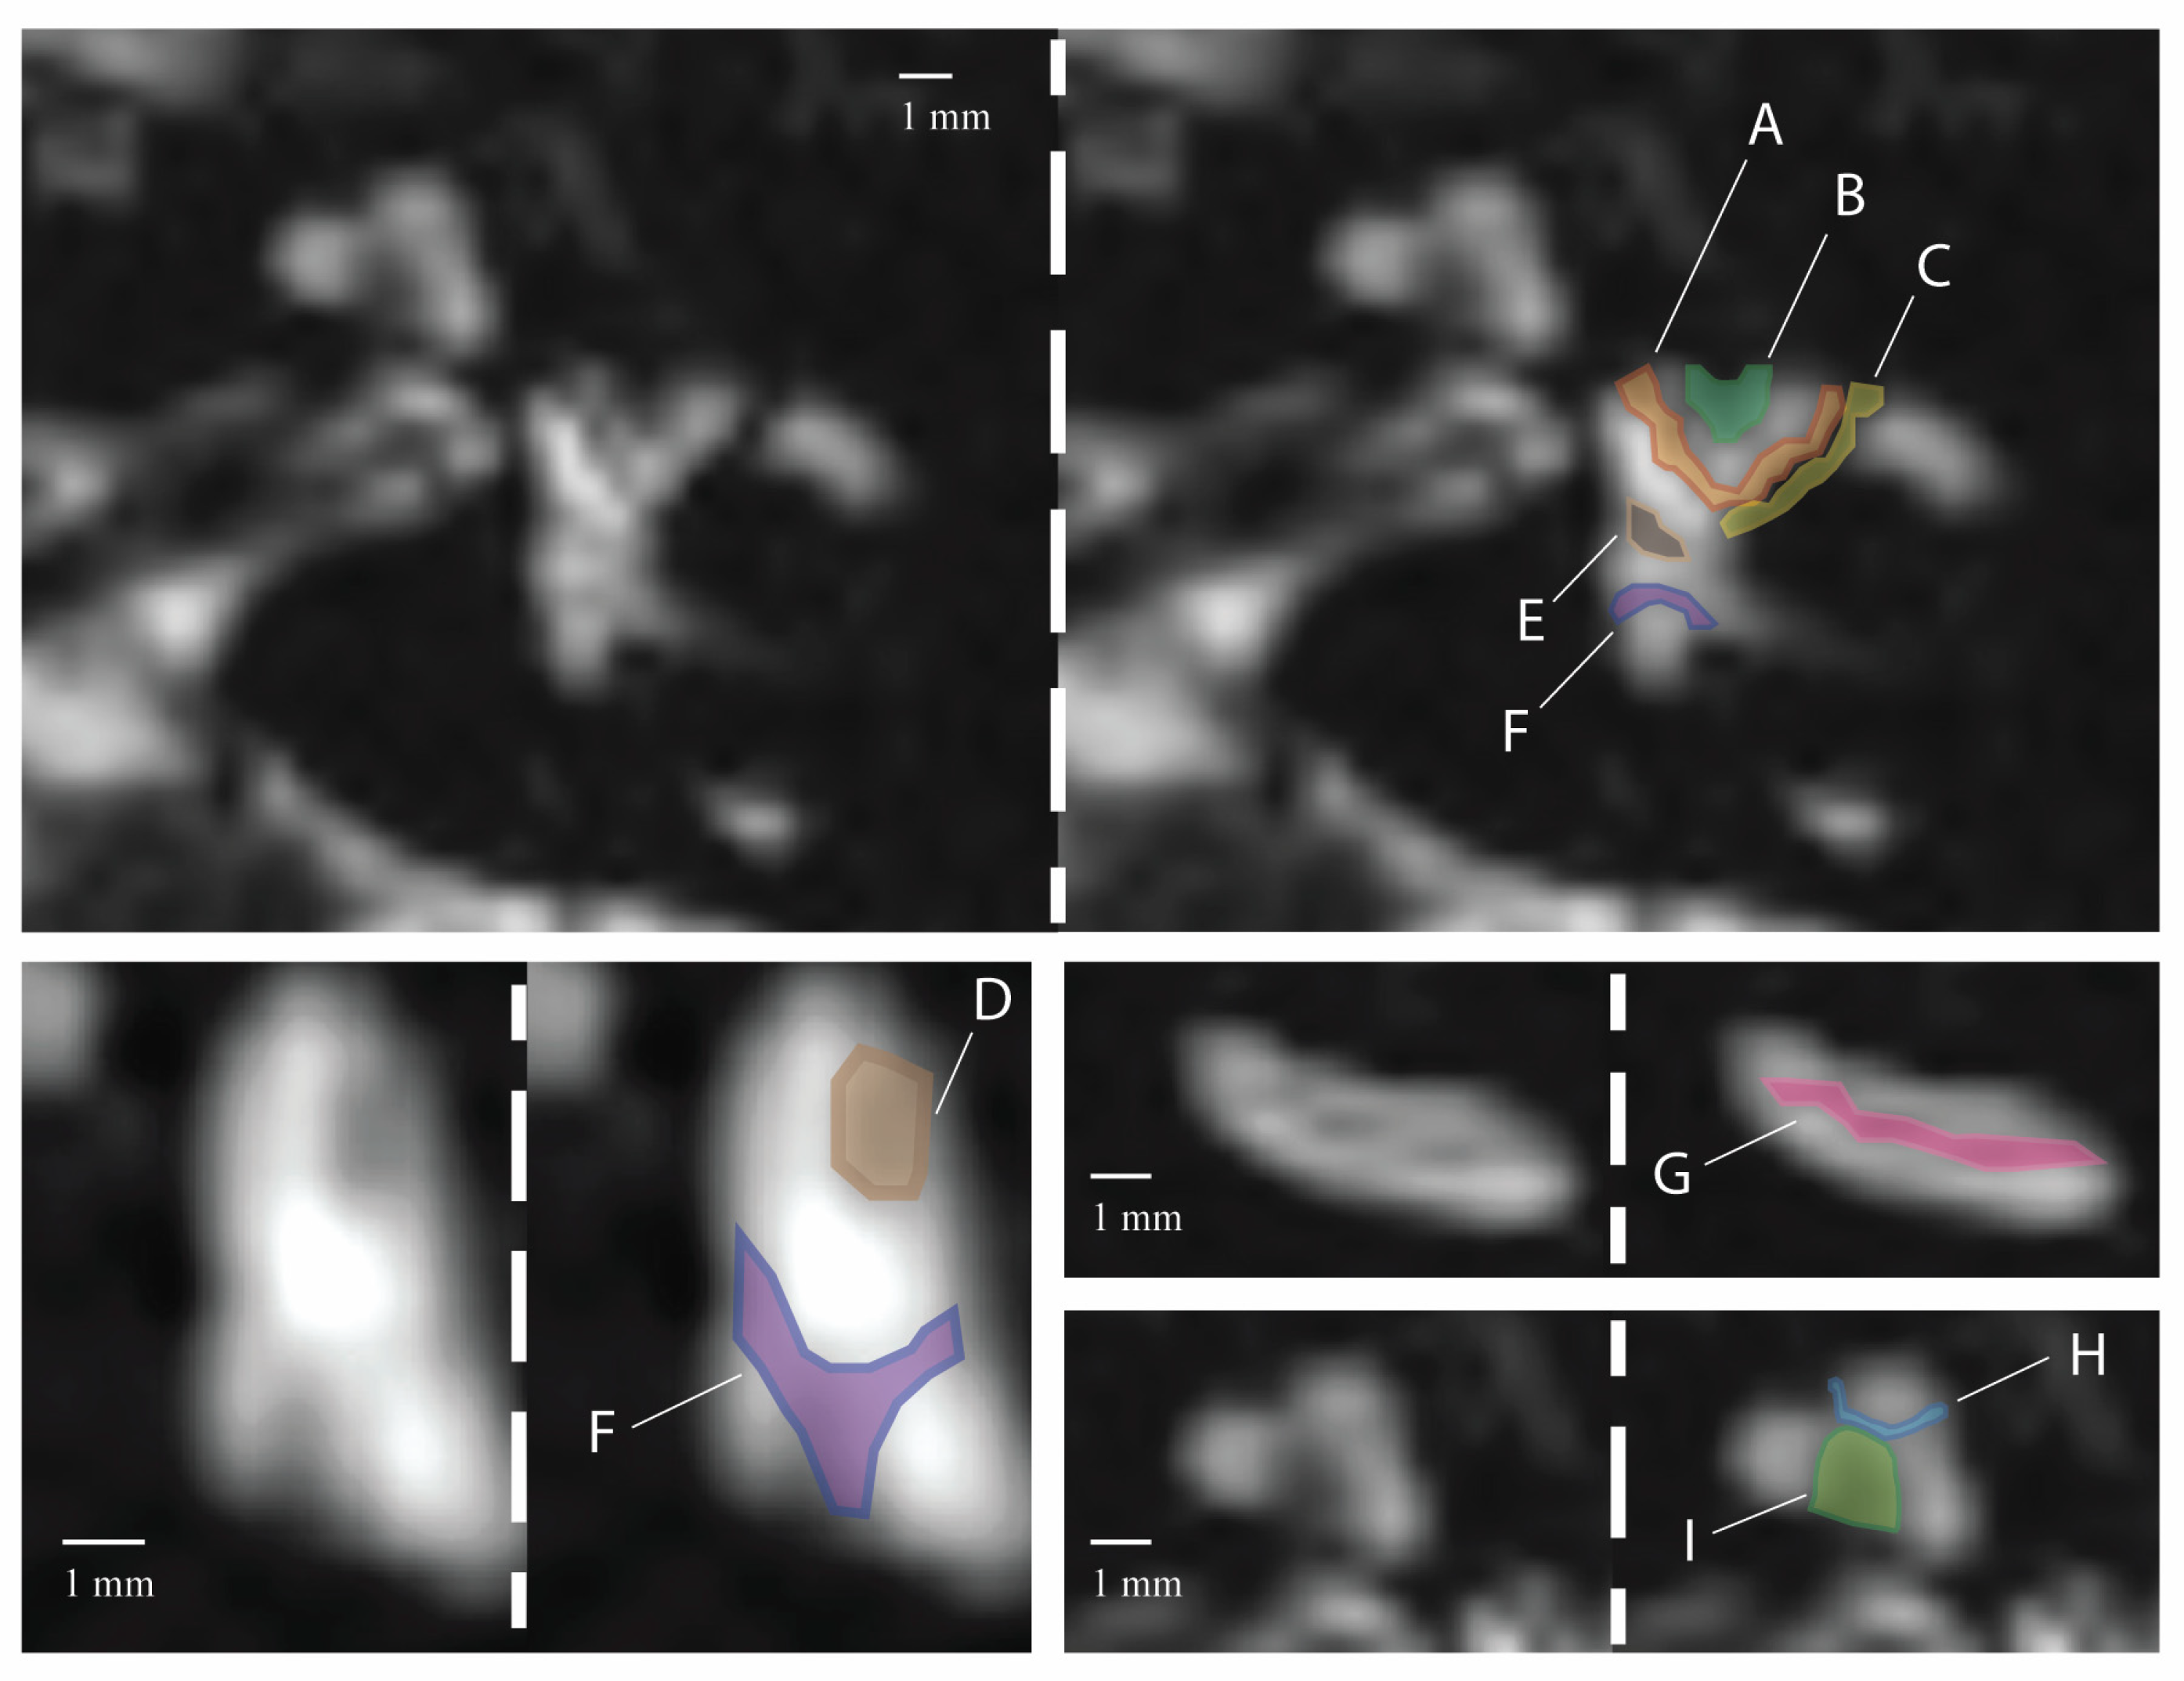

3.1. Signal Areas in the Inner Ear

| Regions of Low Signal Intensity within the Inner Ear (n) | ||||||||||

|---|---|---|---|---|---|---|---|---|---|---|

| A | B | C | D | E | F | G | H | I | ||

| Right ear | Reader 1 | 8 | 6 | 6 | 7 | 9 | 9 | 8 | 10 | 10 |

| Reader 2 | 8 | 6 | 5 | 7 | 9 | 9 | 8 | 9 | 10 | |

| Left ear | Reader 1 | 10 | 7 | 4 | 7 | 10 | 10 | 8 | 10 | 10 |

| Reader 2 | 10 | 7 | 4 | 7 | 10 | 10 | 8 | 10 | 10 | |

| Regions of Low Signal Intensity (n) | |||||||||

|---|---|---|---|---|---|---|---|---|---|

| A | B | C | D | E | F | G | H | I | |

| Right ear | 27 (90.0%) | 21 (70.0%) | 10 (30.3%) | 22 (73.3%) | 28 (93.3%) | 29 (96.7%) | 24 (80.0%) | 29 (96.7%) | 30 (100%) |

| Left ear | 28 (93.3%) | 21 (70.0%) | 14 (46.7%) | 25 (83.3%) | 26 (86.7%) | 29 (96.7%) | 26 (86.7%) | 30 (100%) | 30 (100%) |